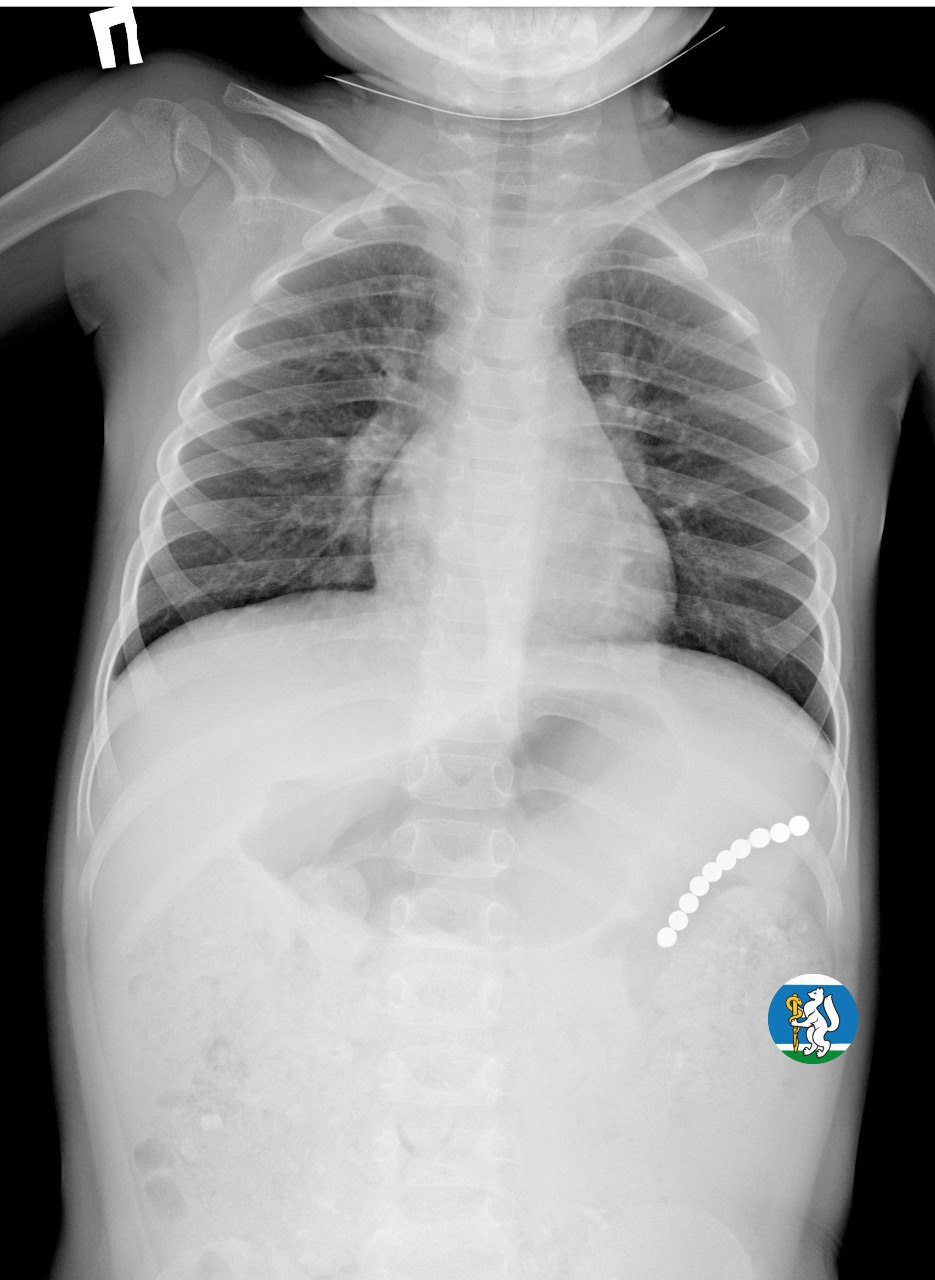

Девочка рассказала родителям о плохом самочувствии, и те показали ее врачам. Медики направили пациентку на рентген грудной клетки. Благодаря обследованию специалисты обнаружили в проекции желудка цепочку магнитов, соединенных между собой. Ребенку сразу же госпитализировали и оказали помощь.

«Для минимизации риска осложнений удаление инородных тел было проведено интраоперационно. В ходе вмешательства дежурная бригада врачей извлекла 10 магнитных шариков, цепочка которых в длину составила 5 сантиметров», — рассказал детский хирург ДГКБ №9 Андрей Чукреев.